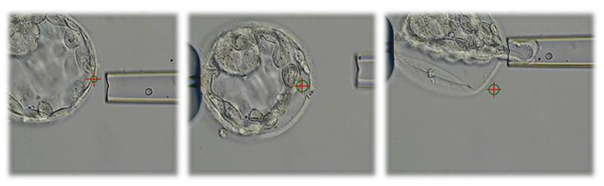

En normal sædcelle suges op i injektionspipette. Ægget holdes fast med en holdepipette, og sædcellen kan forsigtigt stikkes ind i ægget.

Selve biopsi-tagningen foregår ved at skyde et lille hul i embryonets skal. Herigennem suger vi trophectodermceller ud og op i en tynd pipette. Med laseren kan vi adskille de udtagne celler fra resten af de tilbageblevne trophectodermceller.

Med laser skydes der et hul i æggets skal og ved hjælp af pipetten suges celler ud Disse adskilles fra de resterende trophectodermceller ved hjælp af laseren.

Her ses en biopsi, der består af cirka 7 celler i pipetten. Når cellerne er adskilt fra blastocysten, bliver de overført til en anden bakke, hvor de vaskes, lynfryses og sendes til analyse.